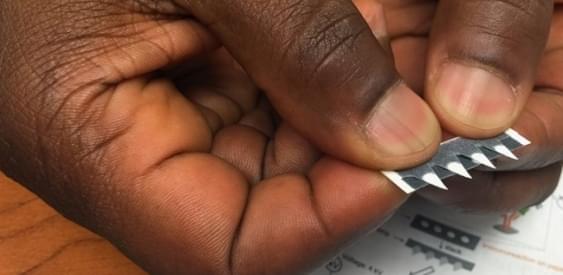

Ученые из Ohio State University создали бумажные тест-полоски, с помощью которых можно диагностировать малярию и некоторые виды рака. Эти тест-полоски стоят очень дешево, и их можно использовать не только в лаборатории, но и в домашних условиях.

Для проведения анализа с их помощью требуется лишь капля крови, которую нужно поместить на специальную бумажную полоску и отправить ее в лабораторию. В том случае, если результат анализа окажется положительным, пациент будет приглашен к врачу, и ему будут назначены дополнительные обследования. Смысл тестов-полосок в том, что человеку не пр

Для проведения анализа с их помощью требуется лишь капля крови, которую нужно поместить на специальную бумажную полоску и отправить ее в лабораторию. В том случае, если результат анализа окажется положительным, пациент будет приглашен к врачу, и ему будут назначены дополнительные обследования. Смысл тестов-полосок в том, что человеку не придется при подозрении на малярию идти к врачу – можно сделать тест дома и отправить его в лабораторию.

По мнению ученых, такие тесты могут использоваться в районах, где риск заражения малярией очень высок. Их также можно применять для диагностики других заболеваний, которые связаны с продукцией специфических антител в организме, например, рака толстого кишечника и рака яичников.

Образцы крови, нанесенные на полоски, будут анализироваться с помощью масс-спектрометрии. Благодаря специальному покрытию полосок, размер которых не будет превышать размера почтовой марки, образец будет защищен от действия света, изменений температуры и влажности. Тест-полоска сможет храниться в течение 30 дней.

Разработчики в течение года проверяли эффективность полосок, диагностируя с их помощью как малярию, так и рак яичников. Теперь они надеются получить лицензию на их массовое производство и начать использовать их в клинической практике. По их словам, стоимость каждой полоски не будет превышать 50 центов.